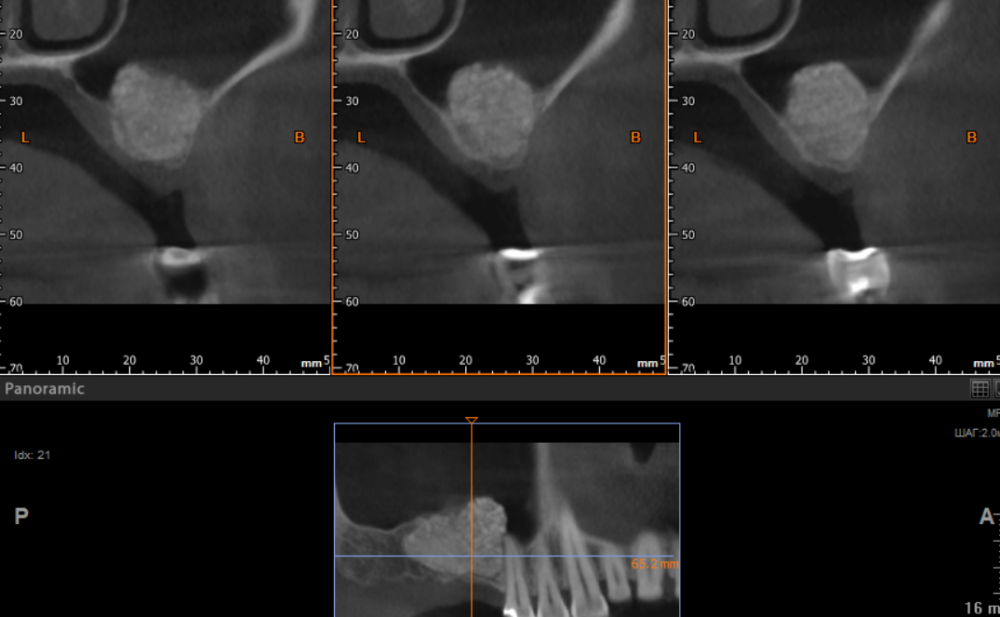

fog7 Опубликовано 5 февраля, 2024 Поделиться Опубликовано 5 февраля, 2024 Добрый день, коллеги, полгода назад был проведён осл, материла было уложено достаточно, перфораций мембраны во время операции не наблюдалось, послеоперационный период без осложнений. В итоге на клкт такая картина. Собираюсь добить зсл и поставить имплантат на 8мм. Скажите, как ведёт себя мембрана после осл, насколько высок риск перфораций? Ссылка на комментарий

fog7 Опубликовано 5 февраля, 2024 Автор Поделиться Опубликовано 5 февраля, 2024 Использовался Biooss s в чистом виде, контрольного клкт непосредственно после операции не проводилось Ссылка на комментарий

kramer Опубликовано 5 февраля, 2024 Поделиться Опубликовано 5 февраля, 2024 (изменено) 3 часа назад, fog7 сказал: Использовался Biooss s в чистом виде Чистый биоосс в пазухе почти не дает усадку. Либо часть графта ушла в пазуху, либо исходно столько и было. Думаю, можно спокойно сделать ЗСЛ Вот здесь было 2 шприца Bio Oss 0,5 L: Изменено 5 февраля, 2024 пользователем kramer 2 Ссылка на комментарий

fog7 Опубликовано 6 февраля, 2024 Автор Поделиться Опубликовано 6 февраля, 2024 Я больше склоняюсь к тому, что причина в не диагностированной перфорации, но это уже история. На сегодняшний момент актуально мнение коллег, как ведёт себя слизистая пазухи при повторных вмешательствах на ней, становится ли она более тонкой, менее прочной, насколько её возможно поднять мм на 3 без риска перфораций? Ссылка на комментарий

Irouil Опубликовано 6 февраля, 2024 Поделиться Опубликовано 6 февраля, 2024 Здесь особо и отслаивать не нужно же, повода для беспокойства не вижу. Стукнуть разок и винт сам вам СЛ сделает 1 Ссылка на комментарий